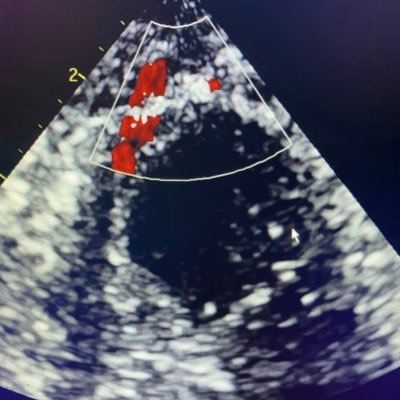

Pre and post mitral TEER, note the improvement in aortic valve opening with increased forward flow..